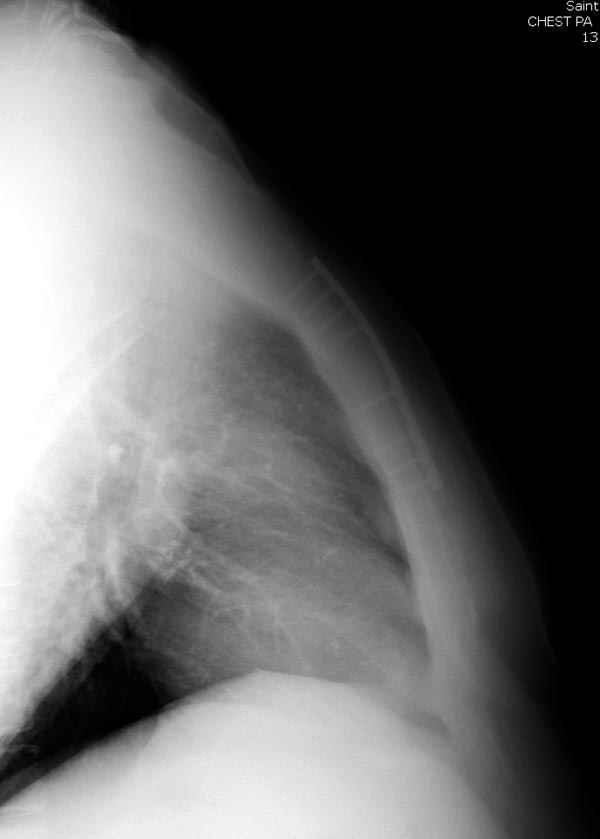

Оперировали вместе с грудным хирургом и в нашем случае главной причиной была болезненность. Во время операции приняли все меры предосторожности недопущения прокола средостения (см. на 4 снимке близкий контур сердца!!)

Рентген снимки во время операции и последние сделаны на днях.